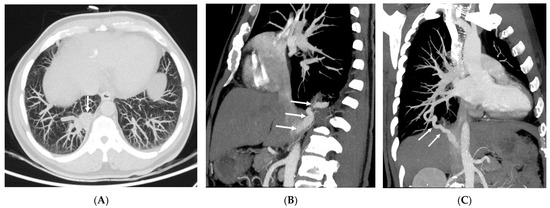

3.2. Imaging Appearances of CTPA